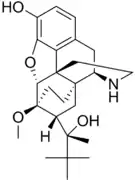

Oripavine derivatives

Thienorphine

- 7-PET

- Acetorphine

- Alletorphine (N-allyl-noretorphine)

- BU-48

- Buprenorphine

- Buprenorphine-3-glucuronide

- Cyprenorphine

- Dihydroetorphine

- Etorphine

- Homprenorphine

- 18,19-Dehydrobuprenorphine (HS-599)

- N-cyclopropylmethylnoretorphine

- Nepenthone

- Norbuprenorphine

- Norbuprenorphine-3-glucuronide

- Thevinone

- Thienorphine

Structures

| Oripavine derivatives | ||||

7-PET 7-PET |

Acetorphine Acetorphine |

Alletorphine Alletorphine |

BU-48 BU-48 |

Buprenorphine Buprenorphine |

Cyprenorphine Cyprenorphine |

Dihydroetorphine Dihydroetorphine |

Etorphine Etorphine |

Homprenorphine Homprenorphine |

18,19-Dehydrobuprenorphine 18,19-Dehydrobuprenorphine |

N-cyclopropylmethylnoretorphine N-cyclopropylmethylnoretorphine |

Nepenthone Nepenthone |

Norbuprenorphine Norbuprenorphine |

Thevinone Thevinone |

Thienorphine Thienorphine |